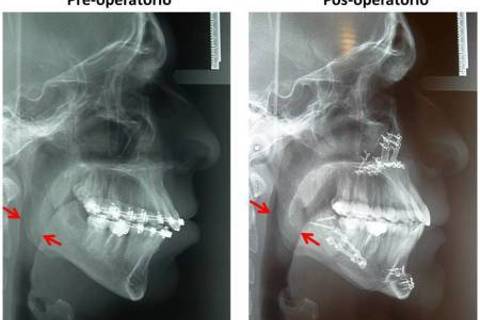

Pós-operatório onde observamos rotação anti-horária do plano oclusal com avanço de mandíbula e mento mais reposicionamento superior de maxila. Note entre as setas o aumento das vias aéreas, o que favorece a diminuição de roncos e episódios de apneia durante o sono.